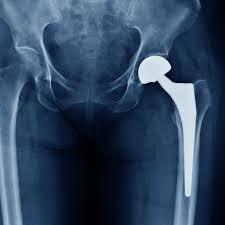

黃贊文說明,黃小姐在外院順利生下小寶貝後,來到他的門診,X光檢查發現是左側髖關節壞死,在安排「微創正前開髖關節置換手術」後,疼痛和長短腳不見了,手術當天下午麻醉藥效一退,就迫不及待下床練習走路,現在不但可以蹲著幫心肝寶貝洗香香,還能像以前一樣跟老公一起去公園散步。

「微創正前開髖關節置換手術」 對肌肉無破壞、術後疼痛減輕恢復快

「微創正前開髖關節置換手術」因為對周圍的肌肉幾乎沒有破壞,術後恢復快、疼痛減輕,可以減少止痛藥使用也不用擔心哺乳問題。另外,行走步態也較穩定,通常病人在術後當天下午即可持助行器走路。由於不需要等待6至8周肌肉愈合時間,大部分的病患僅需要2至4周使用助行器和拐杖。